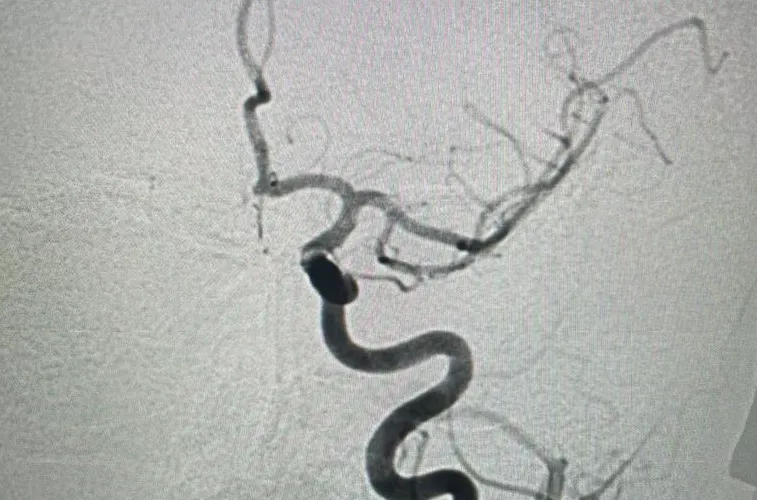

Стентирование сонной артерии